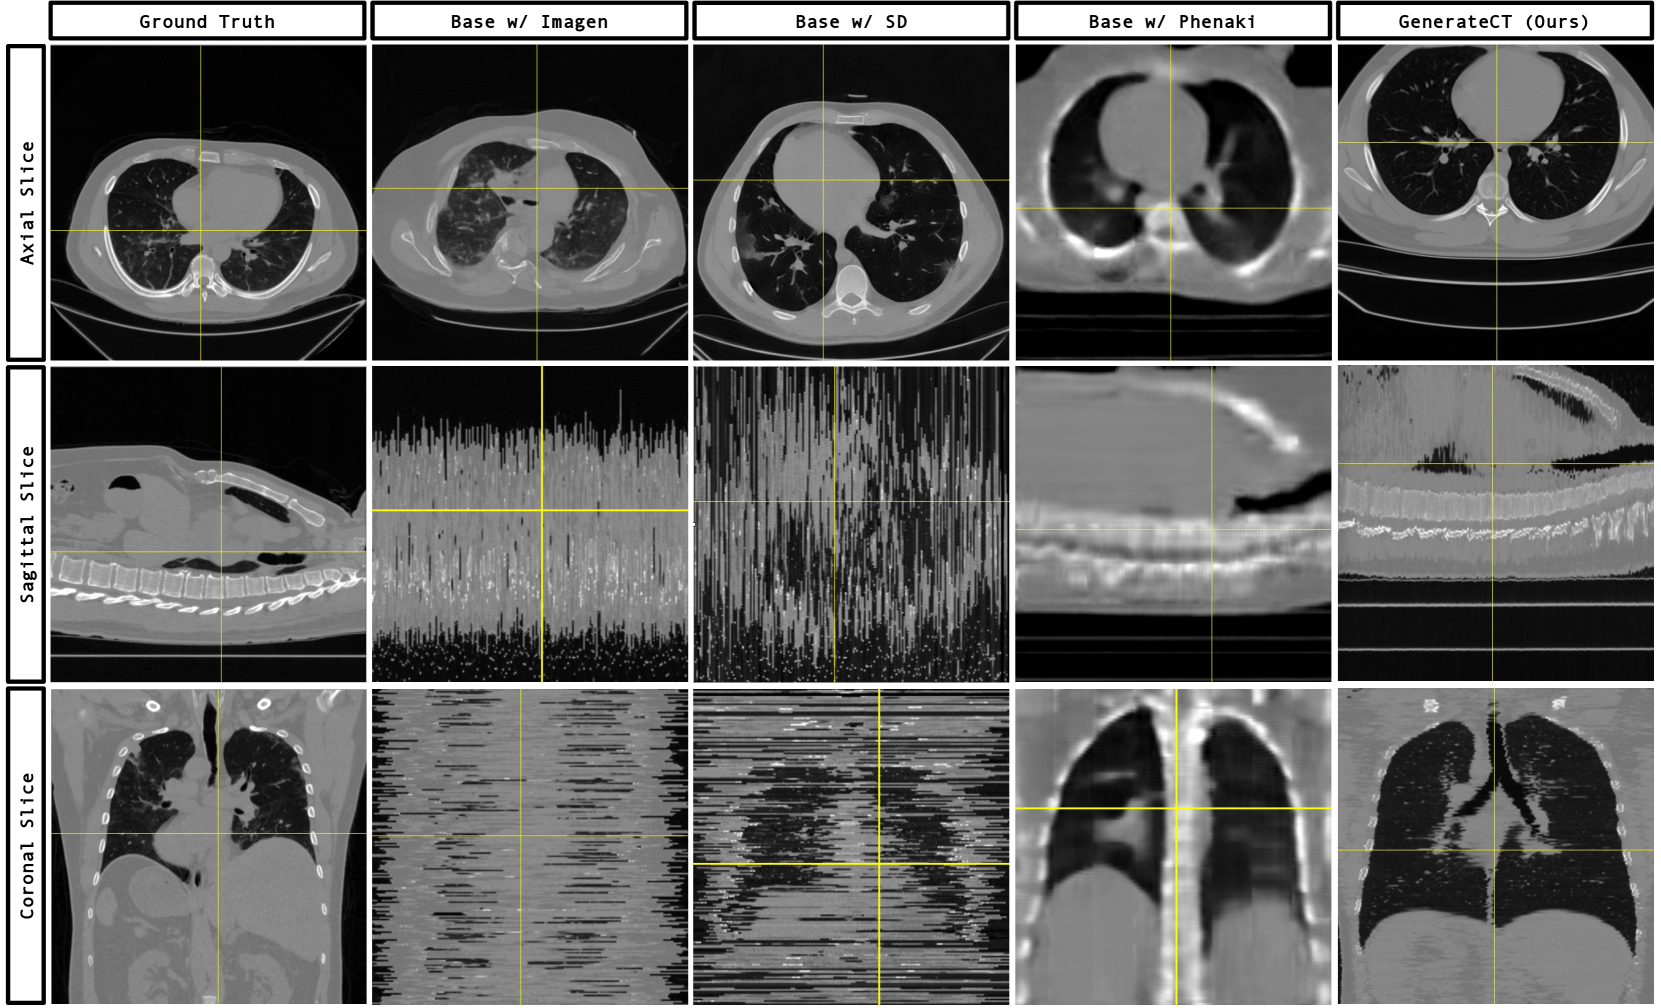

Refer to caption

Figure 3: Axial, sagittal, and coronal slices of ground-truth and synthetic 3D chest CT volumes generated by different methods, based on the text prompt: "26 years old male: Findings compatible with COVID-19 pneumonia". The results showcase GenerateCT’s proficiency in crafting detailed and spatially consistent 3D volumes. Although comparing with ground truth is not customary in text-to-image research, its inclusion here acts as a reference point, highlighting GenerateCT’s ability to produce diverse volumes that accurately align with text prompts, instead of merely replicating training data.

• Base w/ Imagen. To assess the importance of our 3D generation architecture for achieving spatial consistency in 3D chest CT volumes, we employed a text-conditional 2D image generation method, Imagen [34], for slice-wise generation. We conditioned Imagen on the slice number alongside the text prompt during training. Then the generated slices are combined in the order of the conditioning slice number to form a 3D chest CT volume. Fig. 3 shows that, even though high resolution and accurate axial slices were achieved, the chest CT volumes generated by this 2D baseline lack spatial consistency, further highlighting the need for a dedicated 3D generation algorithm.

• Base w/ SD. To demonstrate that even a pre-trained 2D text-to-image model is not sufficient for 3D medical image generation, we fine-tuned Stable Diffusion (SD) [31]. Despite slightly outperforming Imagen, fine-tuning SD failed to produce spatially consistent and accurate 3D volumes, as seen in the sagittal and coronal planes (Fig. 3). This effort also highlighted the computational complexities of direct, text-conditional 3D medical image generation: generating just one 2D axial slice with SD required 13 GB of GPU memory. The memory requirement would escalate exponentially when utilizing a basic 3D diffusion model to generate a 3D chest CT volume consisting of over 200 slices, underscoring its limitations for such medical applications and the imperative for an optimally engineered framework like GenerateCT.

• Base w/ Phenaki. To highlight that even 3D generation models might not capture the nuanced medical details of chest CT volumes, we adapted a state-of-the-art text-to-video generation model, Phenaki [37], for 3D chest CT generation. Although spatial consistency increased, Phenaki failed to generate medically detailed CT volumes (Fig. 3). This underscores the unique challenges of text-conditional high-resolution 3D medical image generation and the necessity for an optimized solution like our cascaded architecture.